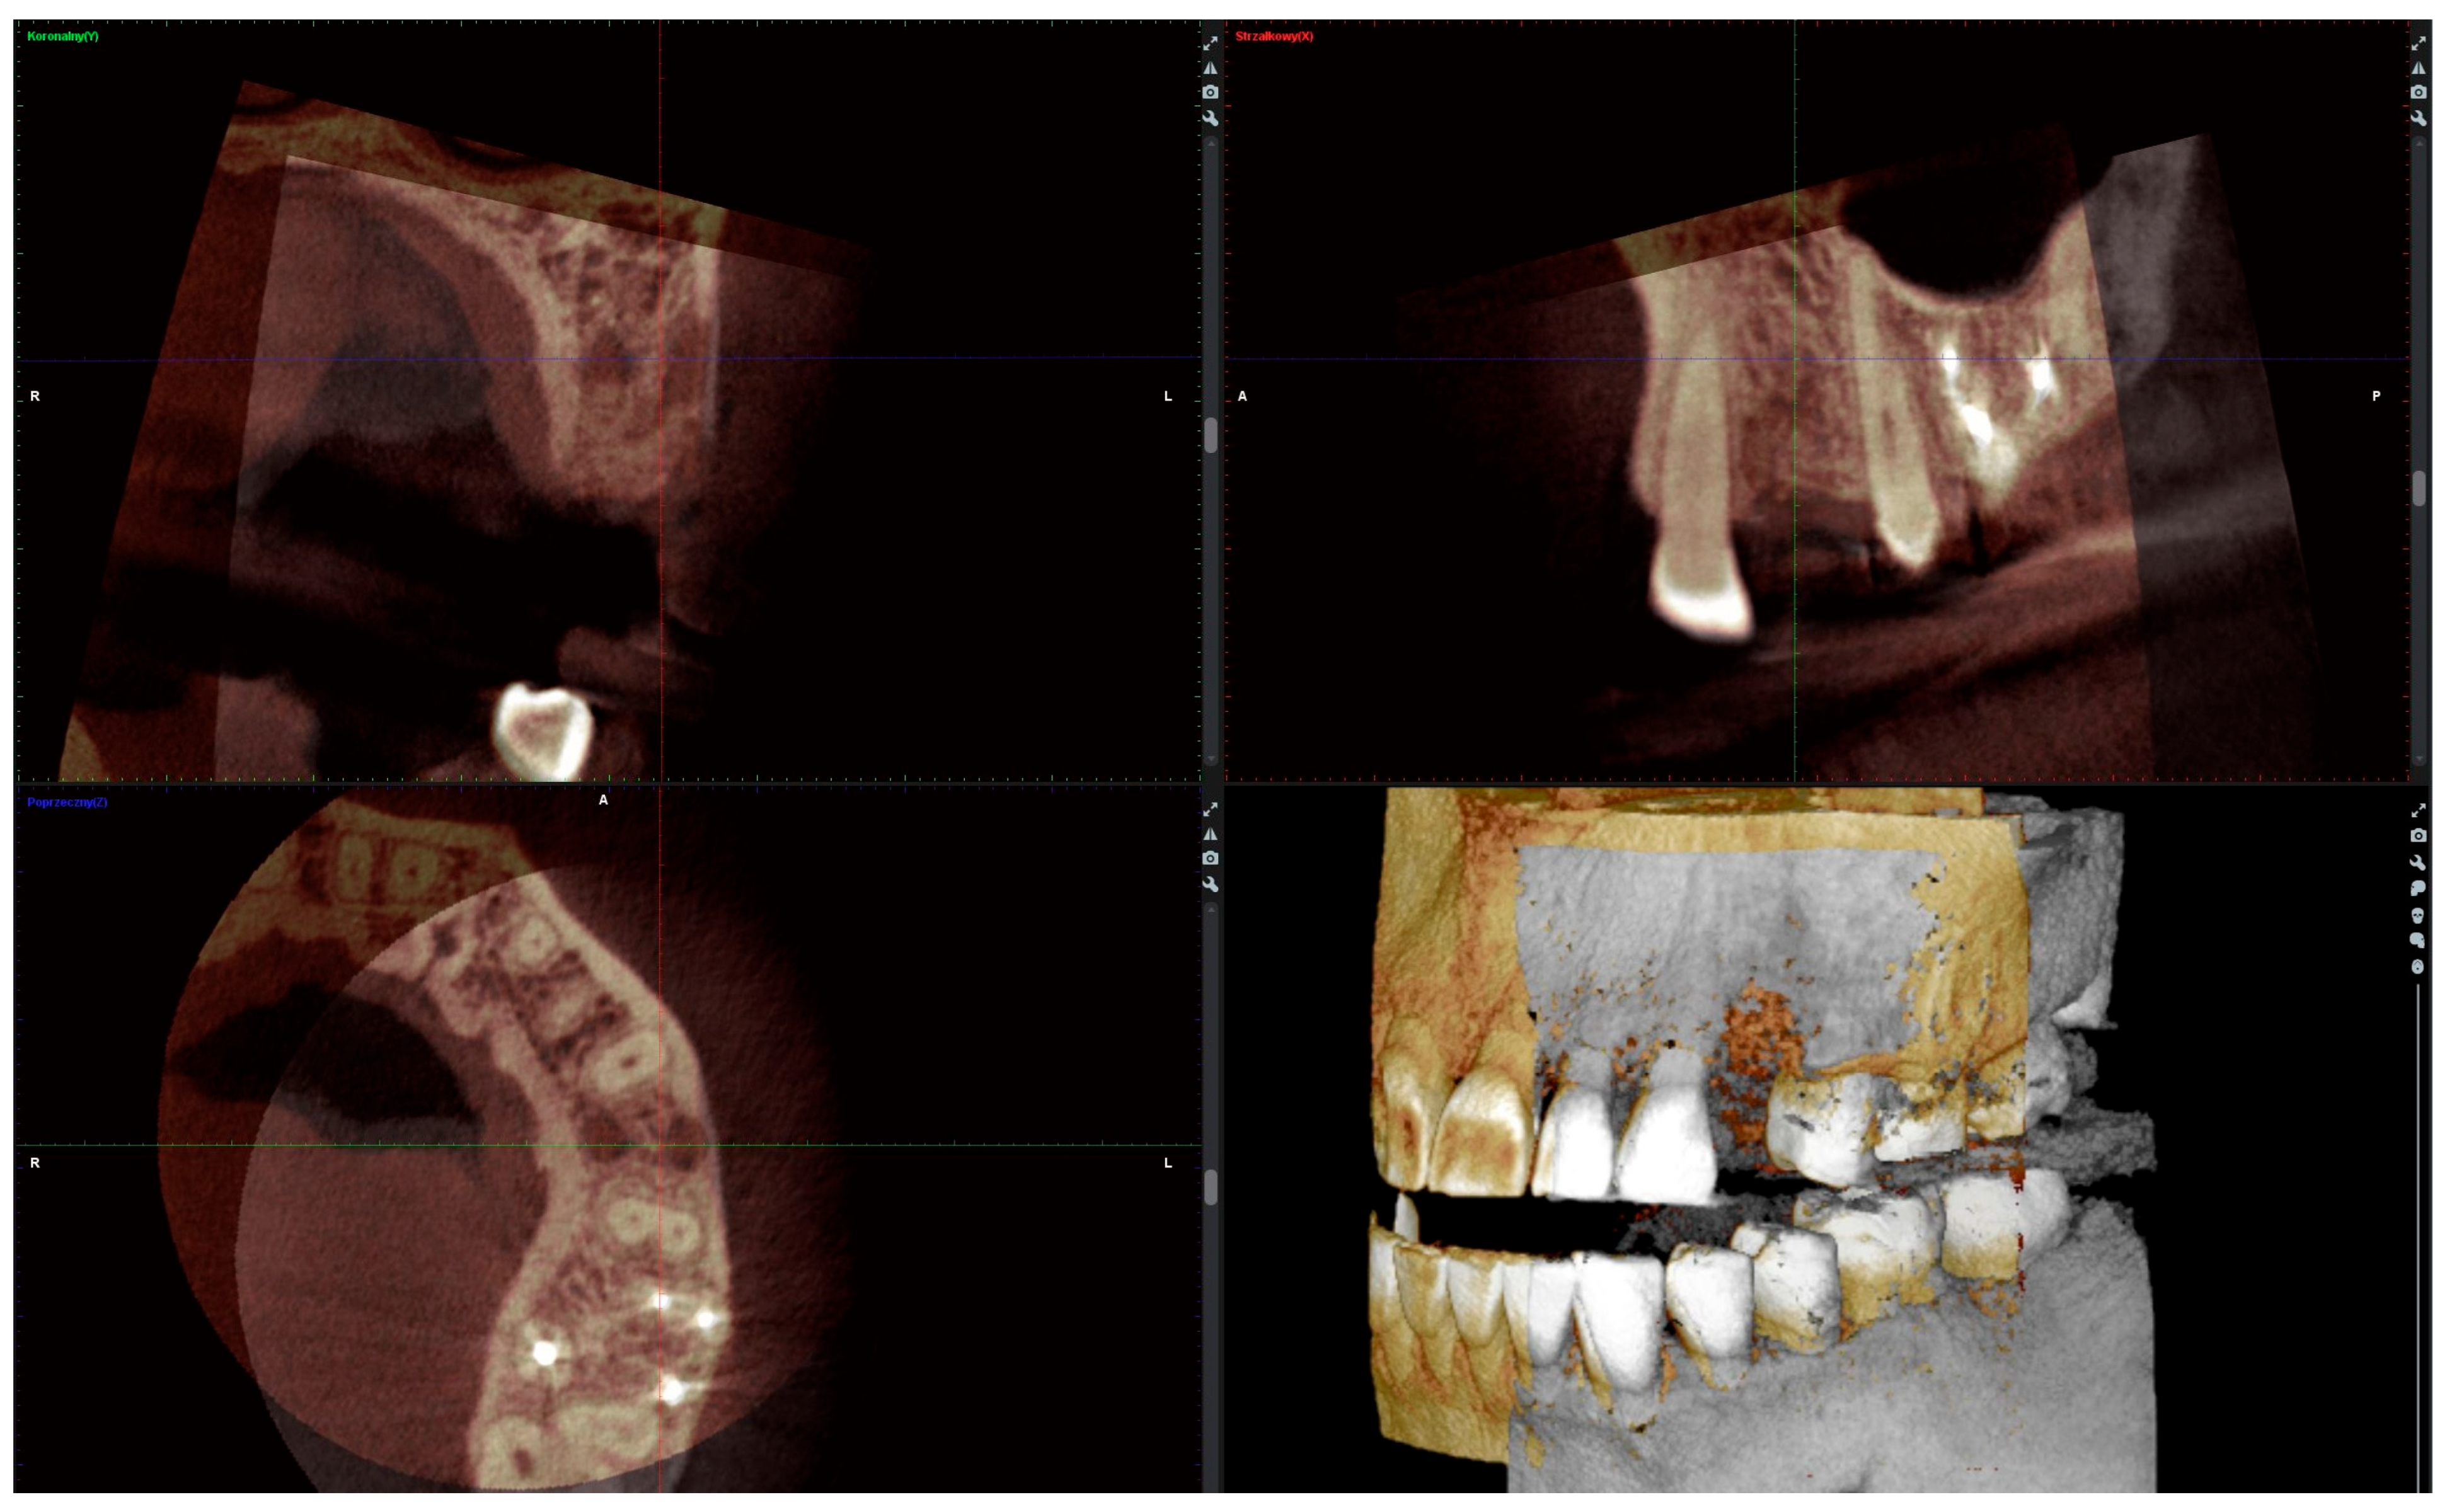

Six months after the socket preservation procedure, another CBCT with a 5 × 5 cm FOV was performed to plan the placement of the implant in the augmented site (Figure 2A).

Figure 2.

(A) Alveolar ridge after 6 months of healing; (B) bone biopsy with trephine; (C) obtained trepanobiopsy; (D) implant secured with cover screw; (E) screw-retained crown restoration.

2.4. Radiographic Analysis

The radiographic analysis consisted of alveolar ridge dimension measurements taken 1 week and 6 months post socket preservation surgery. The measurements were made using the Romexis software provided by the Planmeca company. The superimposition of the radiographic images was created automatically by selecting 3 reference points, most often the incisal edges and cusps of adjacent teeth. Afterward, the images were manually corrected (Figure 3). The above-mentioned steps ensured the repeatability of the measurements carried out on sagittal planes, which were oriented in such a manner that the buccal bone plate was parallel to the long axis. The measurements were made in the central part of the alveolus. The distance between the buccal and palatal bony plates was measured at the alveolar crest, the bottom of the alveolus, and midway between these two points (Figure 4A). The height was measured from the bottom of the alveolus to the top of the buccal and palatal bony plates, respectively (Figure 4B).

Figure 3.

Superimposition of radiographic images.

Figure 4.

(A) Alveolar ridge width measurements: coronally (red line), midpoint (yellow line) and apically (green line); (B) alveolar ridge height measurements: buccally (blue line) and palatally (pink line).